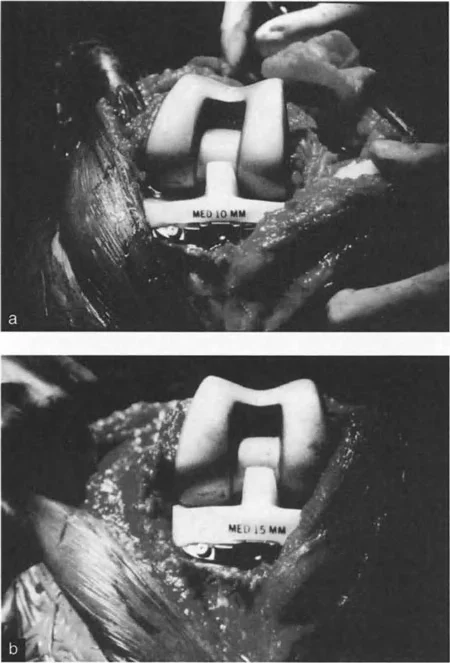

- جراحات قطع العظم وتقويم المحاور

- استبدال المفاصل في حالات التشوه الشديد

في حين أن التشوهات الديناميكية تُناقش غالبًا في سياق أمراض الأعصاب والعضلات لدى الأطفال، فإن المبادئ البيوميكانيكية التي تحكمها تنطبق عالميًا على إعادة بناء العظام لدى البالغين. يشمل ذلك سيناريوهات إعادة البناء المعقدة للغاية، مثل استبدال مفصل الركبة الكلي (TKR) واستبدال مفصل الورك الكلي (THR) المرتبطة بالانحرافات الشديدة خارج المفصل. إن فهم الأذرع الرافعة هو المتطلب الأساسي لإتقان هذه التقنيات المتقدمة في جراحة المفاصل وقطع العظم، وهو ما يتقنه الأستاذ الدكتور محمد هطيف في ممارسته اليومية.